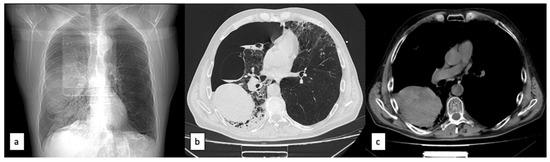

2. Case Report

3.2. Imaging Diagnosis